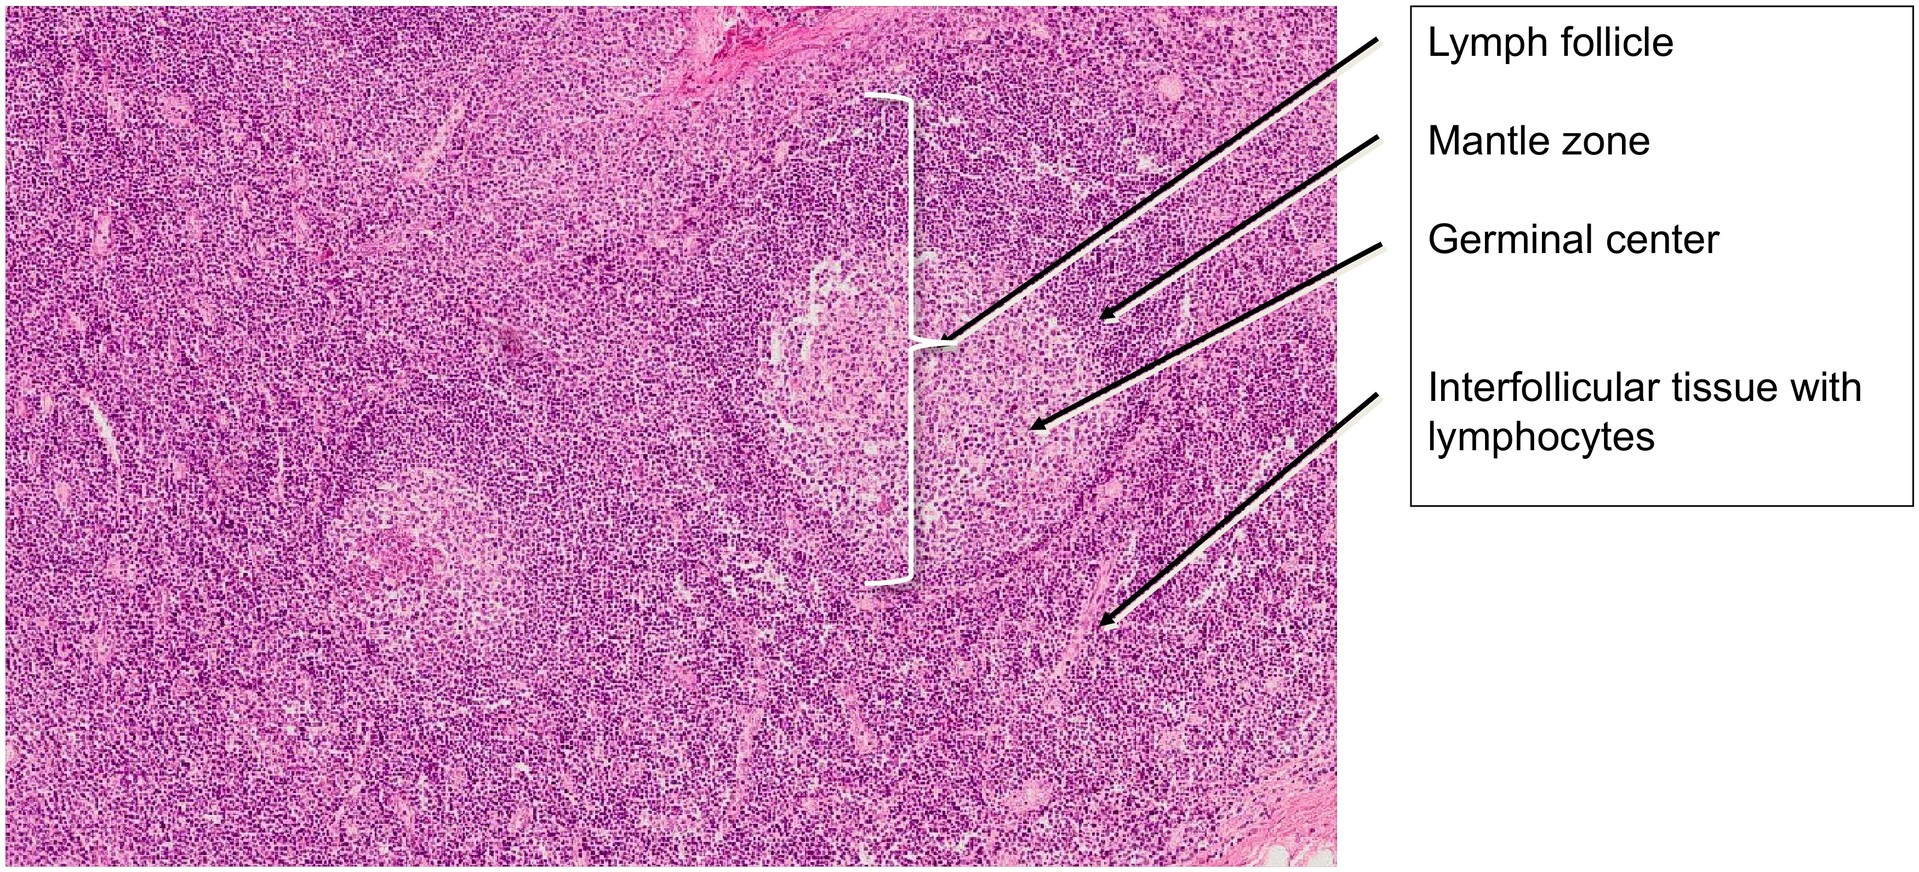

- B-lymphocytes predominate in the lymphatic follicles, which display a light germinal center and a darker mantle zone (lymphocyte shell).

- T-lymphocytes are mainly located in the interfollicular regions, which also contain small blood vessels and capillaries.

Because of the high cellular density, the reticular (lymphoepithelial) framework of the tonsil is difficult to distinguish in the interfollicular areas.

- Examine the lymphatic follicles and describe the difference between the germinal center and the mantle zone.